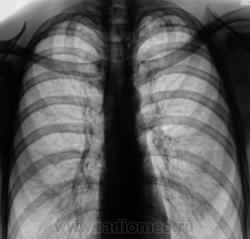

В 2009 году взяли пациента на контроль стандартно дообследовали.

Картинка была типичной, отправили на консультацию к фтизиатру, сделали все необходимые "отметки" в журналах и компе и успокоились, по поводу пациента.

Сравнили две "8" за 2009 и 2010 годы, и вновь, направили пациента на консультацию к фтизиатру.